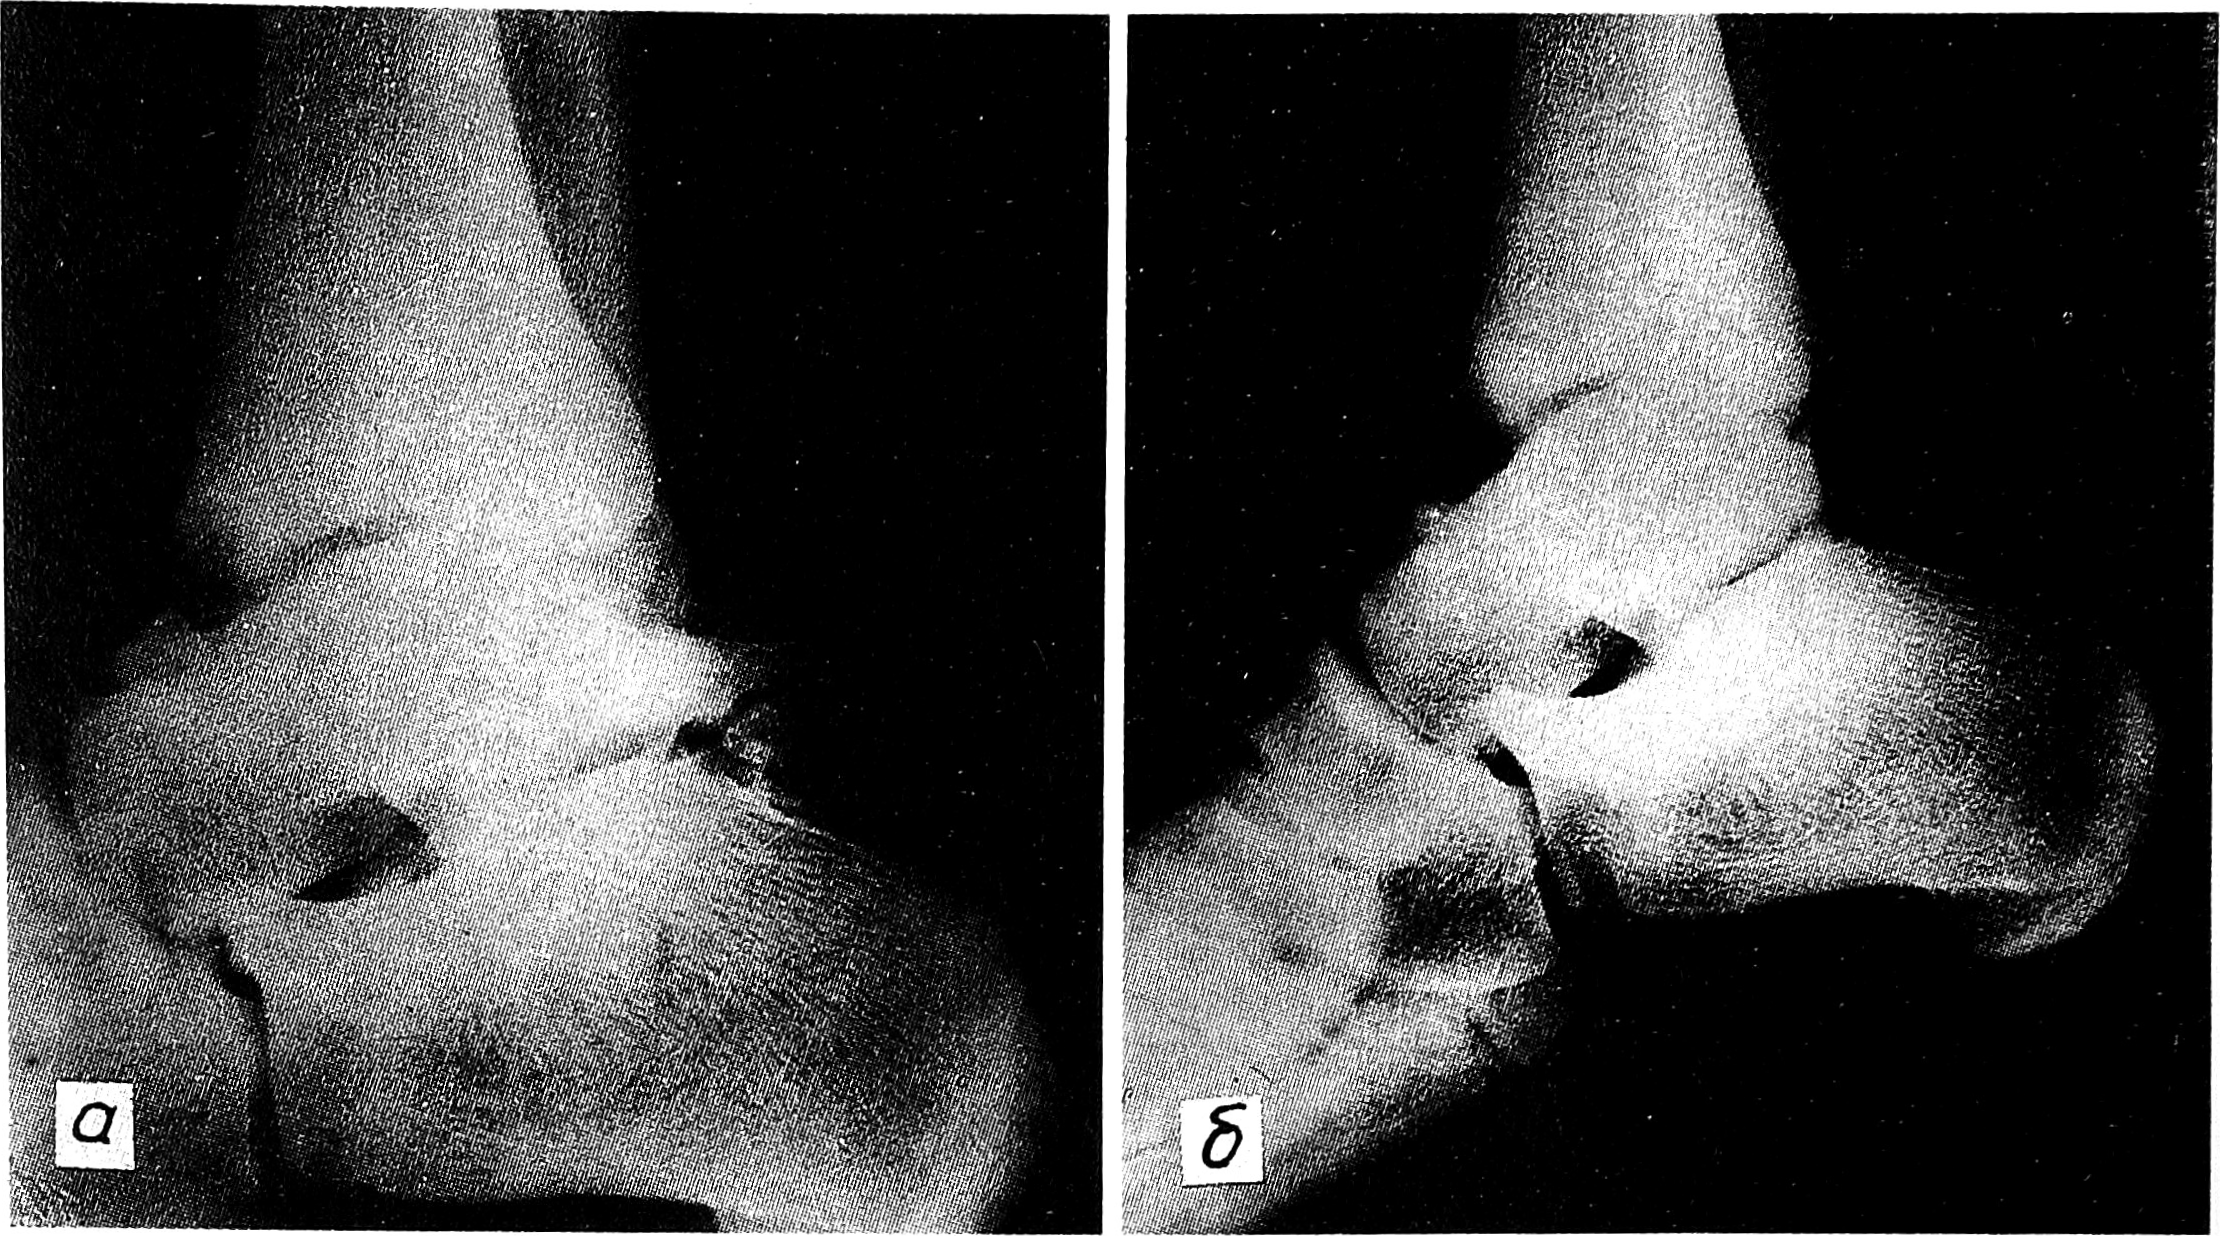

Рентгенография проводилась в боковой проекции, в положении максимального подошвенного сгибания стоп и внутренней их ротации на 30°, что позволяло наилучшим образом вывести на рентгенограммах задний отдел таранной кости. Во всех 9 случаях были выявлены признаки функциональной патологической перестройки заднего отростка таранной кости, выражавшиеся в неравномерности его контуров и наличии линейного разрежения костной структуры в области основания. Вместе с тем мы не исключаем и возможности развитая ахиллоталярного синдрома как следствия наличия треугольной кости. В 3 наших наблюдениях изменения в заднем отделе таранной кости сочетались с оссификацией заднего отдела капсулы голеностопного сустава (см. рисунок на вклейке, а).

Рис. 1. Рентгенограммы голеностопного сустава (боковая проекция) больного с ахиллоталярным синдромом.

а — до операции: патологическая функциональная перестройка заднего отростка таранной кости в сочетании с оссификацией заднего отдела капсулы голеностопного сустава; б — после оперативного лечения (резекции патологически измененного заднего отростка таранной кости и иссечения оссификатов).

Всем пациентам проводилось оперативное лечение, заключавшееся в резекции измененного заднего отростка таранной кости, иссечении оссификатов заднего отдача капсулы голеностопного сустава, измененных участков паратенона и синовиальной сумки ахиллова сухожилия (см. рисунок, б). Кроме того, у 2 больных, у которых на операции были выявлены большие участки дегенерации ткани сухожилия, произведено их иссечение с замещением дефектов лоскутами из апоневроза икроножной мышцы.